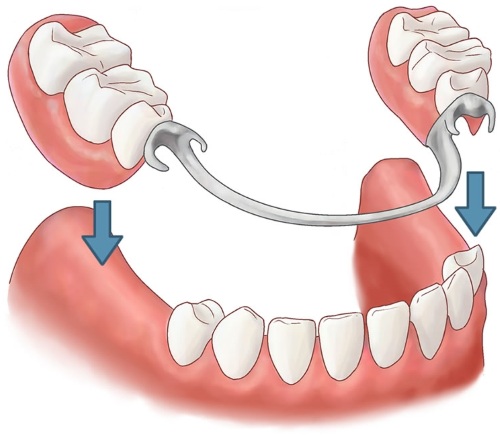

Бюгельный протез на челюсть, фото которого можно встретить для каждого конкретного вида, представляет собой съемную или несъемную конструкцию, в основе которой лежит использование бюгеля – специальной дуги из металла с закрепленными на ней элементами из пластмассы. В конечном итоге протез полностью имитирует внешне здоровую челюсть.

| На кламмерах | Приспособления внешне выглядят, как крючок, который цепляется за 2 крайних опорных зуба на 2/3 их окружности. |

На кламмерах

Кламмеры – это особые типы фиксирующих элементов, которые могут представлять собой конструкции с несколькими деталями:

- плечо – создает достаточную упругость и подвижность системы и располагается вокруг коронки зуба, оно в обязательном порядке выполняется абсолютно гладким, чтобы не травмировать окружающие ткани;

- тело – основная часть конструкции, которая после установки протеза будет контактировать с пищей и напитками;

- отросток – способствует фиксации протеза на постоянном месте и находится под пластиковыми элементами.

Итоговая конструкция в результате без каких-либо повреждений выдерживает повседневную нагрузку.